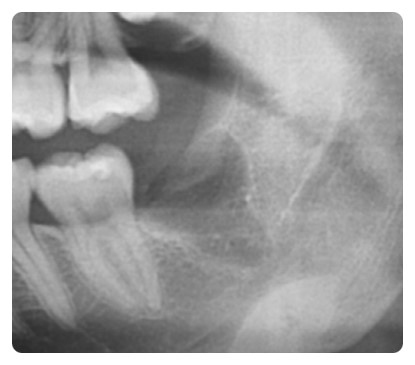

결과적으로 이렇게 깔끔하게 사랑니가 제거가 되었습니다.

사랑니를 뽑고 난 뒤 엑스레이 사진입니다.

주변의 잇몸뼈를 전혀 건드리지 않고 깔끔하게 발치가 되었습니다.

사랑니 발치 후 많은 주의사항이 있습니다.

그중에서도 보시는 것처럼 상당히 깊은 곳에서 발치를

했기 때문에 지혈이 잘 되지 않습니다.

사랑니를 뽑은 후 엑스레이 사진입니다.